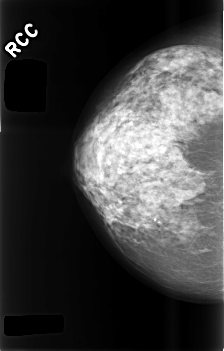

C_0495_1.RIGHT_CC

RIGHT_CC LINES 4552 PIXELS_PER_LINE 2912 BITS_PER_PIXEL 12 RESOLUTION 50 NON_OVERLAY